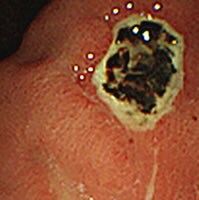

内視鏡検査による症例

胃潰瘍

胃痛があり胃カメラをしたところ胃潰瘍がありました。胃痛の原因と考え、その後お薬をしっかり飲んでいただき、きれいに治ってます。